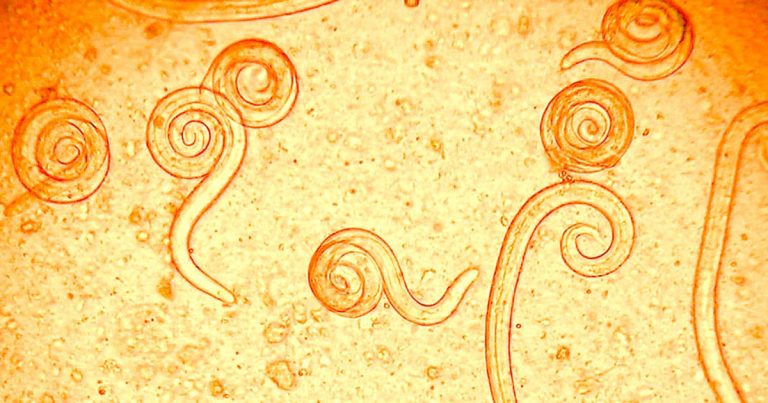

Lungworms are parasitic roundworms that primarily affect the respiratory system of dogs. They belong to the Angiostrongylus and Crenosoma species, with Angiostrongylus vasorum being one of the most common and concerning types for dogs. This infection occurs when a dog inhales or ingests the larvae of these worms, which are typically transmitted through snails, slugs, and other invertebrates. The larvae then travel through the dog's body to the lungs, where they mature into adult worms. Lungworm infections can be fatal if not diagnosed and treated promptly.

3. The Life Cycle of Lungworms

Understanding the life cycle of lungworms is crucial in preventing the infection and recognizing its potential risks. The process begins when the dog ingests or inhales the larvae, which are usually carried by intermediate hosts like snails and slugs. Once inside the dog's body, the larvae travel to the heart and lungs, where they mature into adult worms.

The adult worms release eggs that hatch into larvae. These larvae then enter the bloodstream and are excreted by the dog through its feces. The larvae are then consumed by snails, slugs, or other intermediate hosts, continuing the cycle. The presence of snails and slugs in outdoor areas where dogs roam significantly increases the chances of infection.